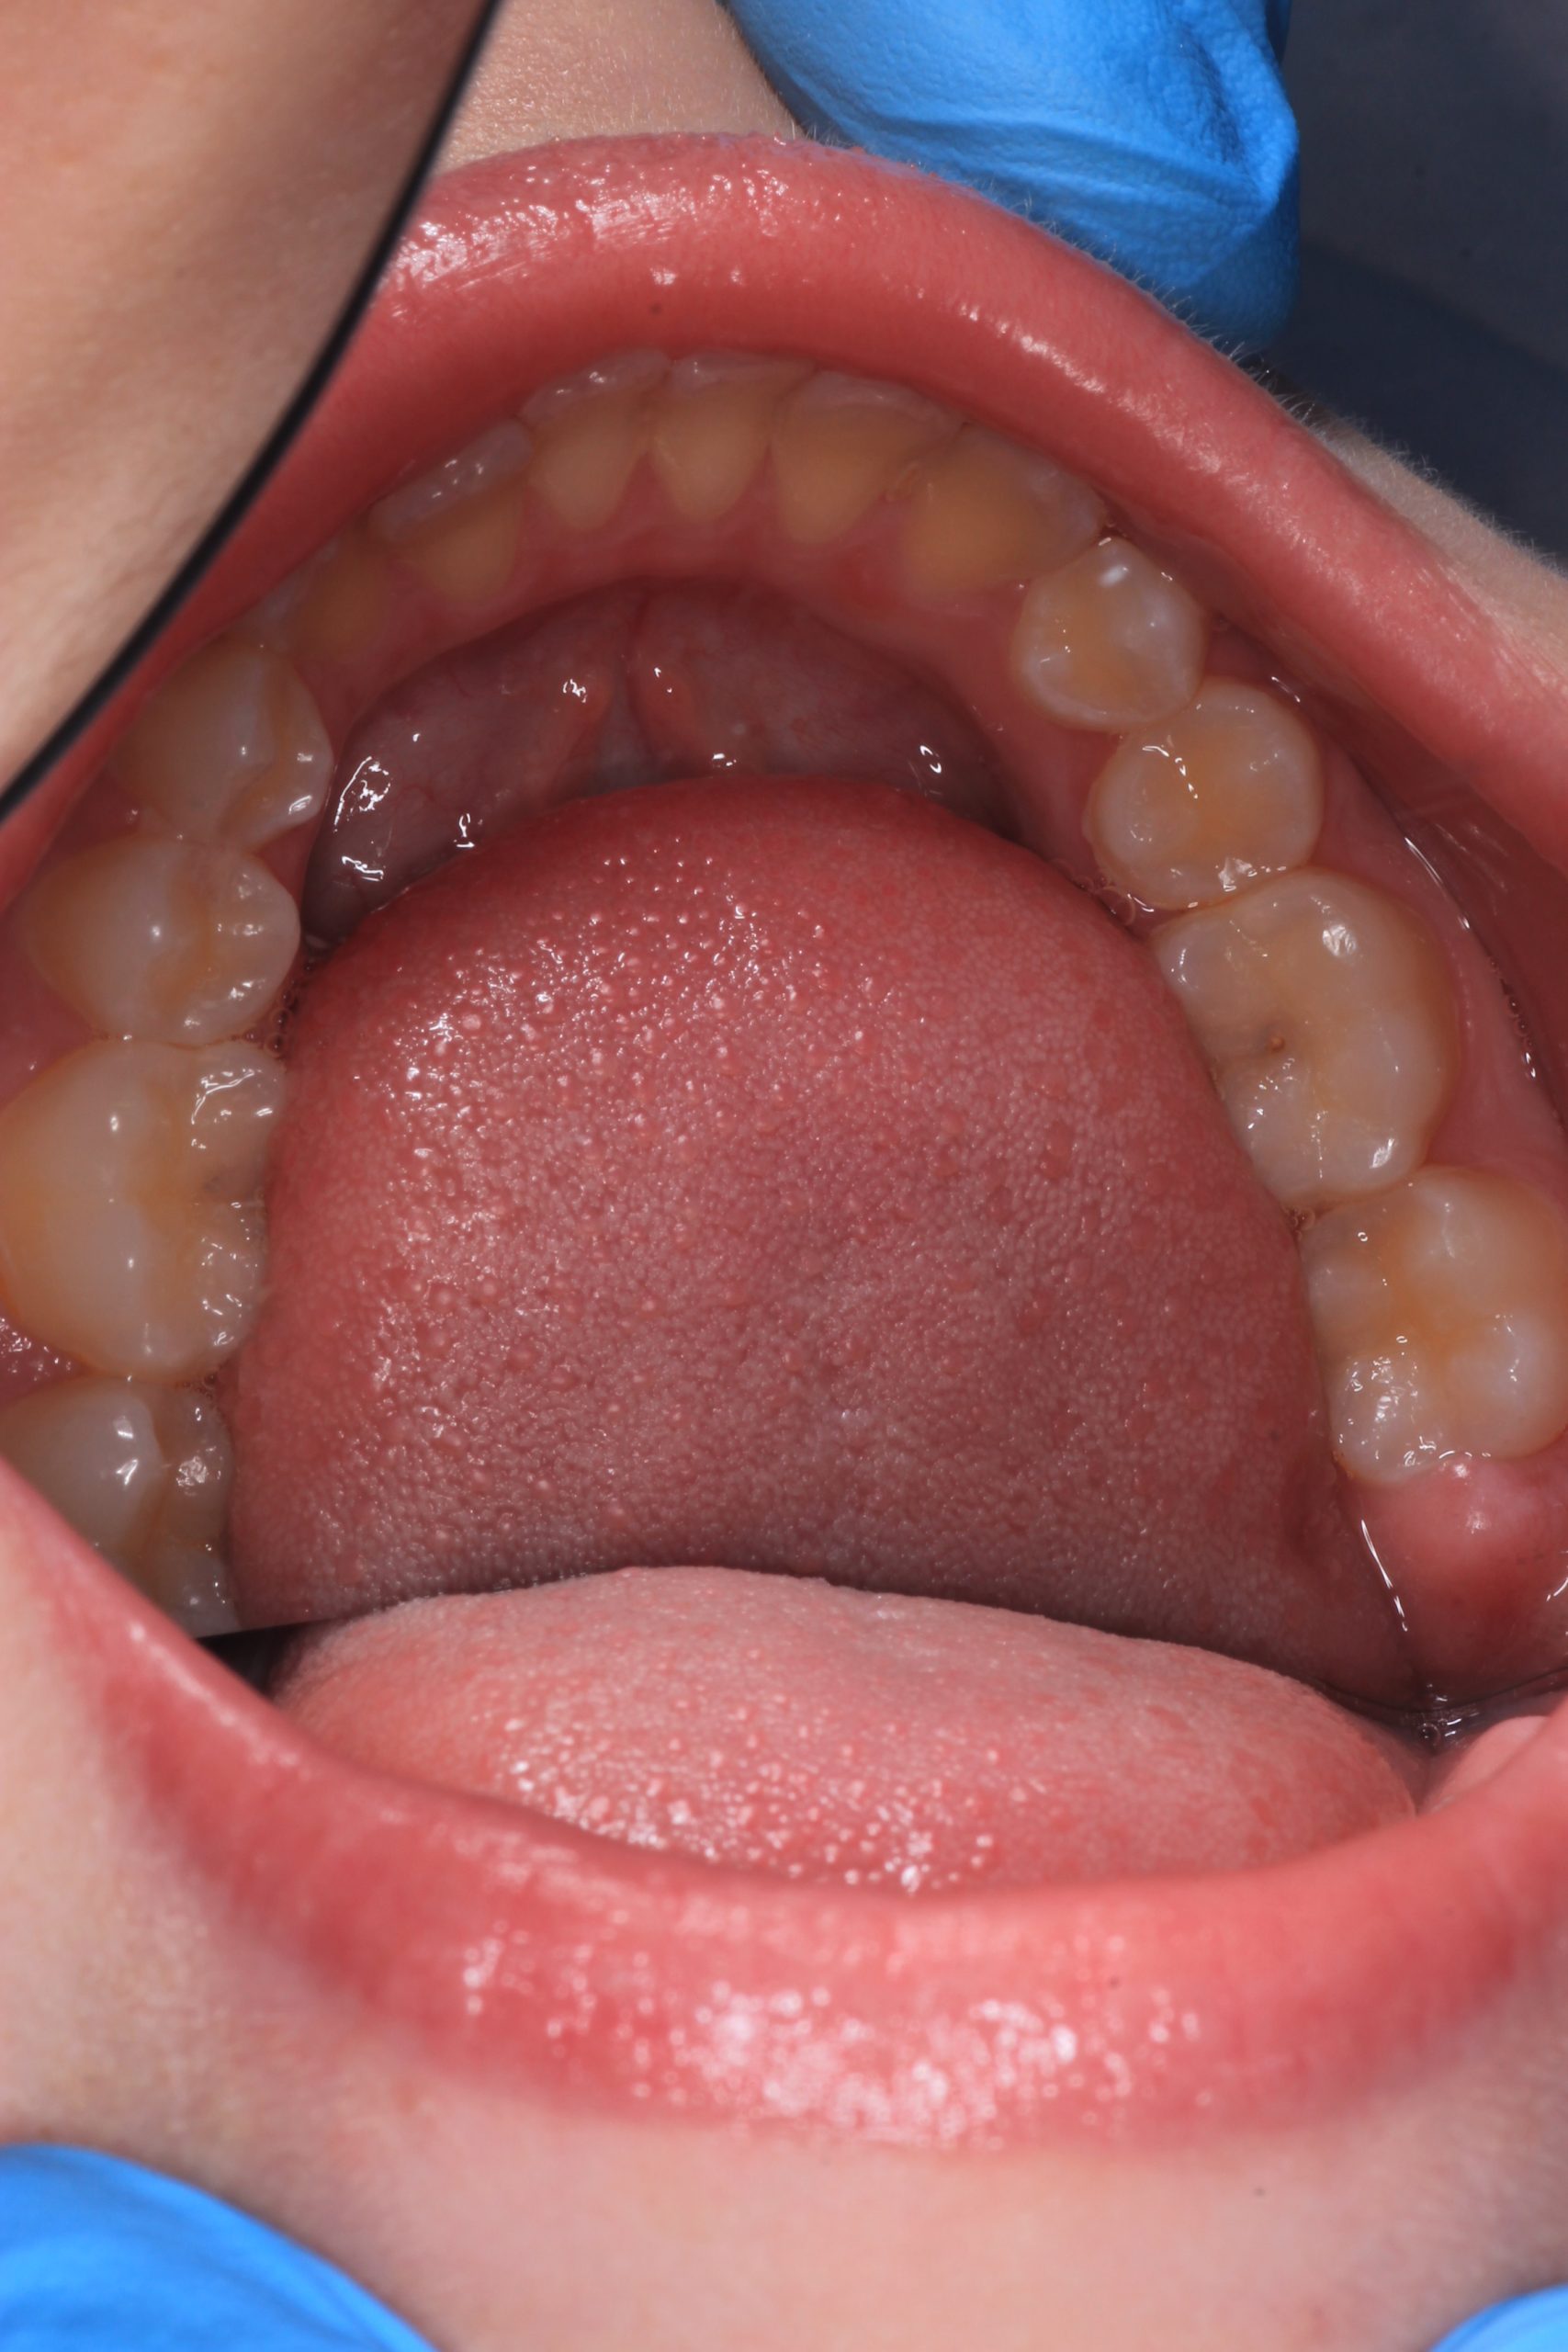

We examine the condition of teeth, gums, and bite. - Plaque Disclosure with Special Indicators

Areas that weren’t cleaned well appear purple. The darker the shade, the older the plaque. This helps both kids and parents understand where brushing needs to improve. - Brushing Training & Home Care Tools Selection